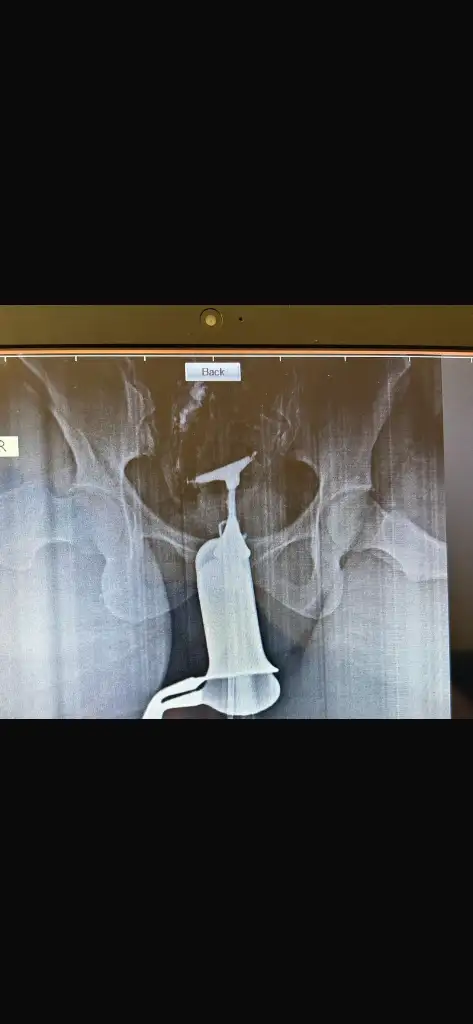

T rahim nasıl oluyor benimde rahmim ters ama doktor bunun gebeliğe ve bebeğe hiç bir etkisi olmadığını söylediAh canım ilk o 5 gebeliği 4 sene içinde yaşadım ama son iki senedir gebe kalamıyordum 6 senelik evliyim ha aralarda düşükler zamanı korunduk ama dediğim gibi son iki senedir gebe kalamadım soğuya tayinim çıktı derken akışına bıraktım Bursa doğru düzgün doktor da yok hep olur diye bekledim yani t rahmi ögrenene kadar düşün rahim filmini de zorla çektirdim doktor gerek yok deyip duruyordu yaşımda 34 şuan neler yaşadım bu kısaca özeti de inşallah sağlıkla ilerler evet sebebi bulamayınca en son t rahimden dolayı dendi iyi bir profa gitmiştim başka şehirde hatta bana bu rahimle gebe kalman bile mucize demişti normalde rahim şekil bozuklukları gebeliğe de engelmiş

Canım tek doktorla kalma burda da öyle yazanlar oldu ama herkeste etkisi farklı doktor bana t rahimle gebe kalman bile mucize olmuş şuana kadar dedi bak doktorlara güvenmemeyi şurdan öğrendim ilk gebelik kayıplarım olurken doktora tabi farklı doktor bu hocam rahim filmi çekeyim dedikçe gerek yok dedi tüplerin açık gebe kalabiliyorsun dene olur deyip durdu bende dinledim onu sonra baktım olmuyor rahim filmi çektirdim farklı bir yerde ve çeken doktor gayet güzel dedi sorun yok dedi anestezili çekildiğim için görüntüyü merak ettim bir açtım ki bariz t rahimdi atarım size fotosunu özelden sonra 3 4 farklı doktora attım filmi hepsi bu t rahim histeroskopi gerek dediler ve iyi bir profa gidip muayene oldum ameliyatımı o yaptı yani demem o ki bazı doktorlar gerçekten hiç bir şey bilmiyorT rahim nasıl oluyor benimde rahmim ters ama doktor bunun gebeliğe ve bebeğe hiç bir etkisi olmadığını söyledi

Dogustan sanırım kürtajla ilgisi yoktur canım Oyüzden histeroskopi diye bir ameliyat var zaten şekil olarak t olduğu için t rahim deniyor bazıları y rahim bazıları kalp benim bariz t idi baksanaCanım nasıl açılıyor bilmiyorum burdan paylaşabilirsin istersen internetten baktım biraz dar sanırım bebeğin yerleşmesi için sıkıntılı. Doğuştan mı böyle geçirilen bir kürtaj veya operasyondan dolayı mı

Aaa şaşırdım gerçekten ameliyat olup bu problem ortadan kalktıysa sorun yok çok şükür. Umarım bebeğinizide sağlıklı bi şekilde kucağınıza alırsınız darısı bizim başımıza inşallah bizede dua edin :)Dogustan sanırım kürtajla ilgisi yoktur canım Oyüzden histeroskopi diye bir ameliyat var zaten şekil olarak t olduğu için t rahim deniyor bazıları y rahim bazıları kalp benim bariz t idi baksana